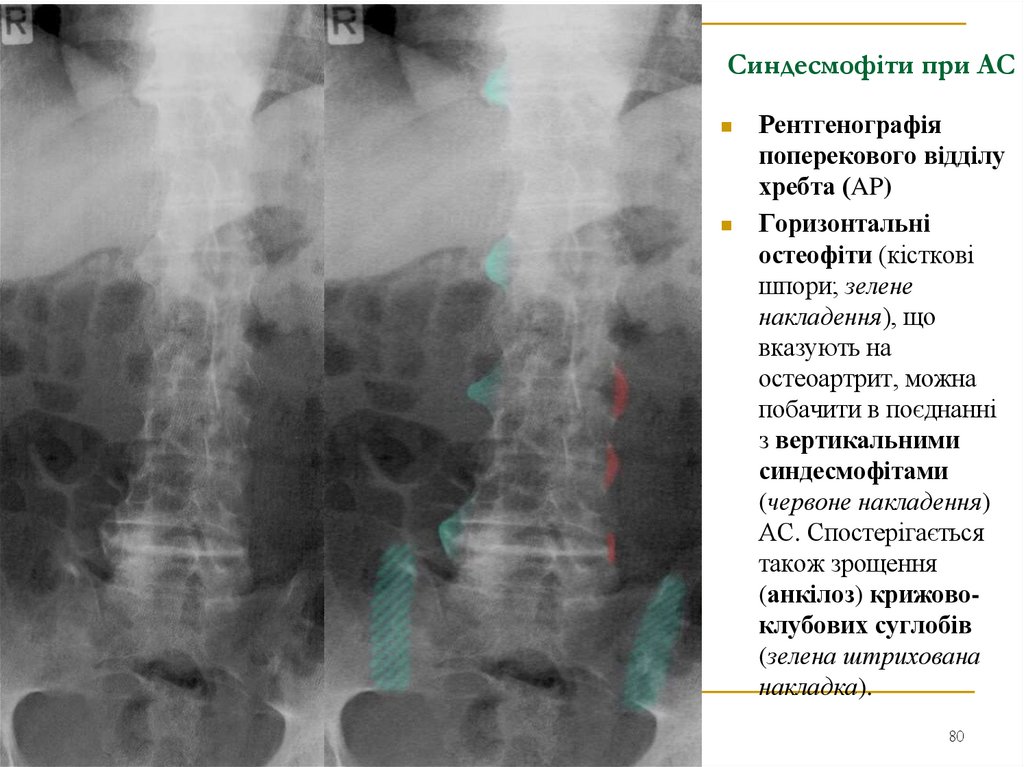

80. Синдесмофіти при АС

Рентгенографія

поперекового відділу

хребта (AP)

Горизонтальні

остеофіти (кісткові

шпори; зелене

накладення), що

вказують на

остеоартрит, можна

побачити в поєднанні

з вертикальними

синдесмофітами

(червоне накладення)

АС. Спостерігається

також зрощення

(анкілоз) крижовоклубових суглобів

(зелена штрихована

накладка).

80